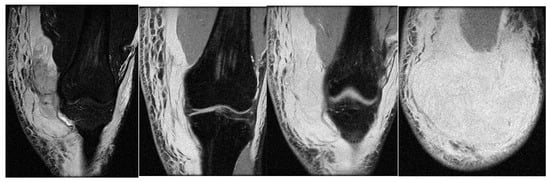

3.3. Case 3: Adductor Complex Strain

In the third case, a left winger reported experiencing sharp pain in the inner left thigh, which severely impaired both active and passive movements during sprints. The left winger, aged 32, has 14 years of experience as a first-league professional in Romania and is a national team member from an urban area, standing 189 cm tall and weighing 90 kg. MRI confirmed the diagnosis of tears and disinsertion of the short adductor tendon and I- and II-degree tears of the obturator externus, pectineus, and adductor longus muscles. STIR sequences show the disinsertion of the short adductor tendon with a gap between the tendon and pubis, with the presence of significant hyperintense alterations, which were also present in the obturator externus, pectineus, and adductor brevis muscles, representing various degrees of fiber tears associated with blood clots (Figure 8).

Figure 8.

(a) Thigh MRI: coronal stir acquisition, (b) thigh MRI: coronal stir acquisition, (c) thigh MRI: axial stir acquisition.

As the reinsertion of the adductor brevis muscle involved an unacceptable period of incapacitation, the adductor magnus, the strongest muscle in the adductor group, being unimpaired, conservative treatment was applied, the player started a physical therapy program focusing on healing first- and second-degree muscle damage, respectively, the hypertonicity and hypertrophy of the other adductor muscles, mainly of the adductor magnus, the strongest muscle in the group. He returned to play after 6 weeks.